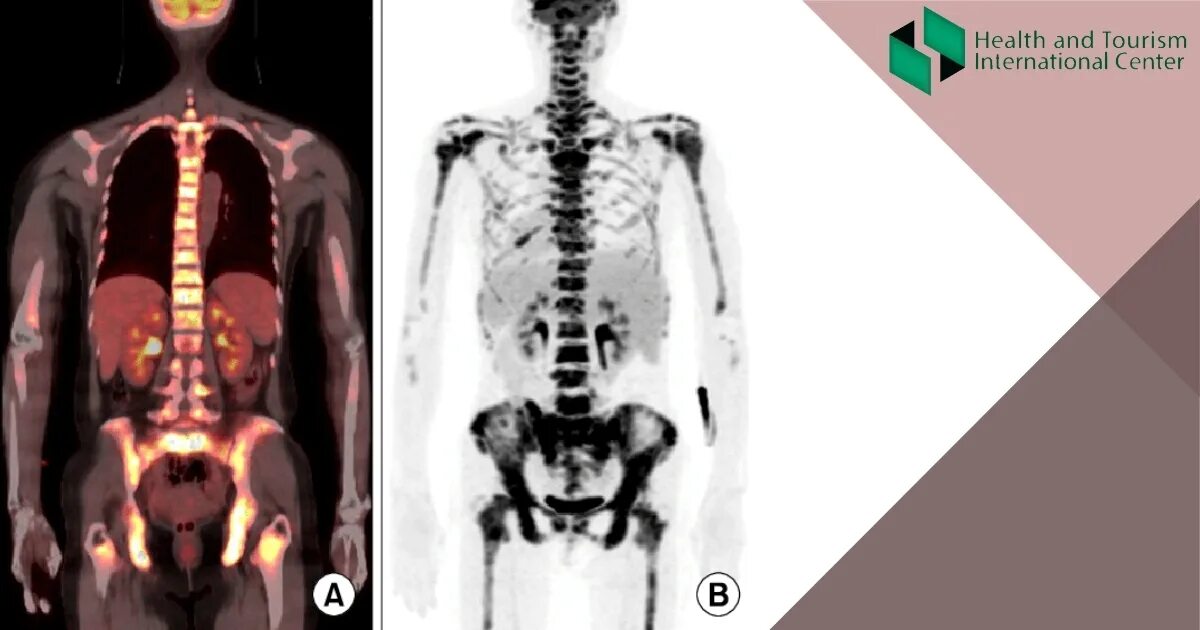

Метастазы костей можно вылечить